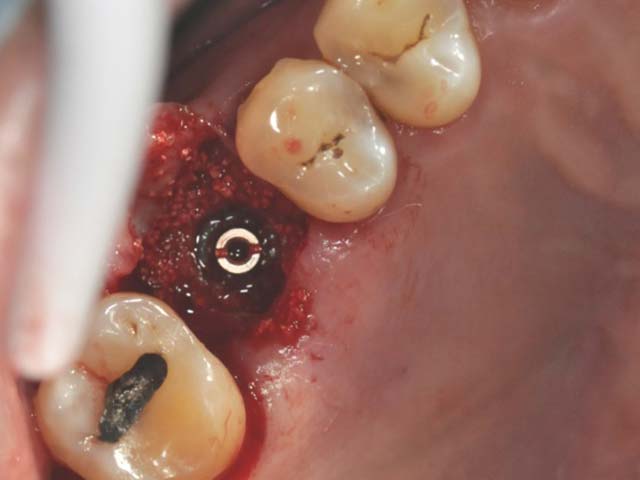

鼻竇增高術(垂直)+植牙 首頁 案例分享 人工植牙 鼻竇增高術(垂直)+植牙 鼻竇增高術(垂直)+植牙 術前評估 PRF(使用法國離心機,萃取出有益於傷口癒合的血小板,並加以濃縮) 鼻竇增高術 從植牙傷口置入萃取的PRF,將鼻竇往上抬升,再植入骨粉,以利植牙。 電腦斷層—術前,術中,假牙完成